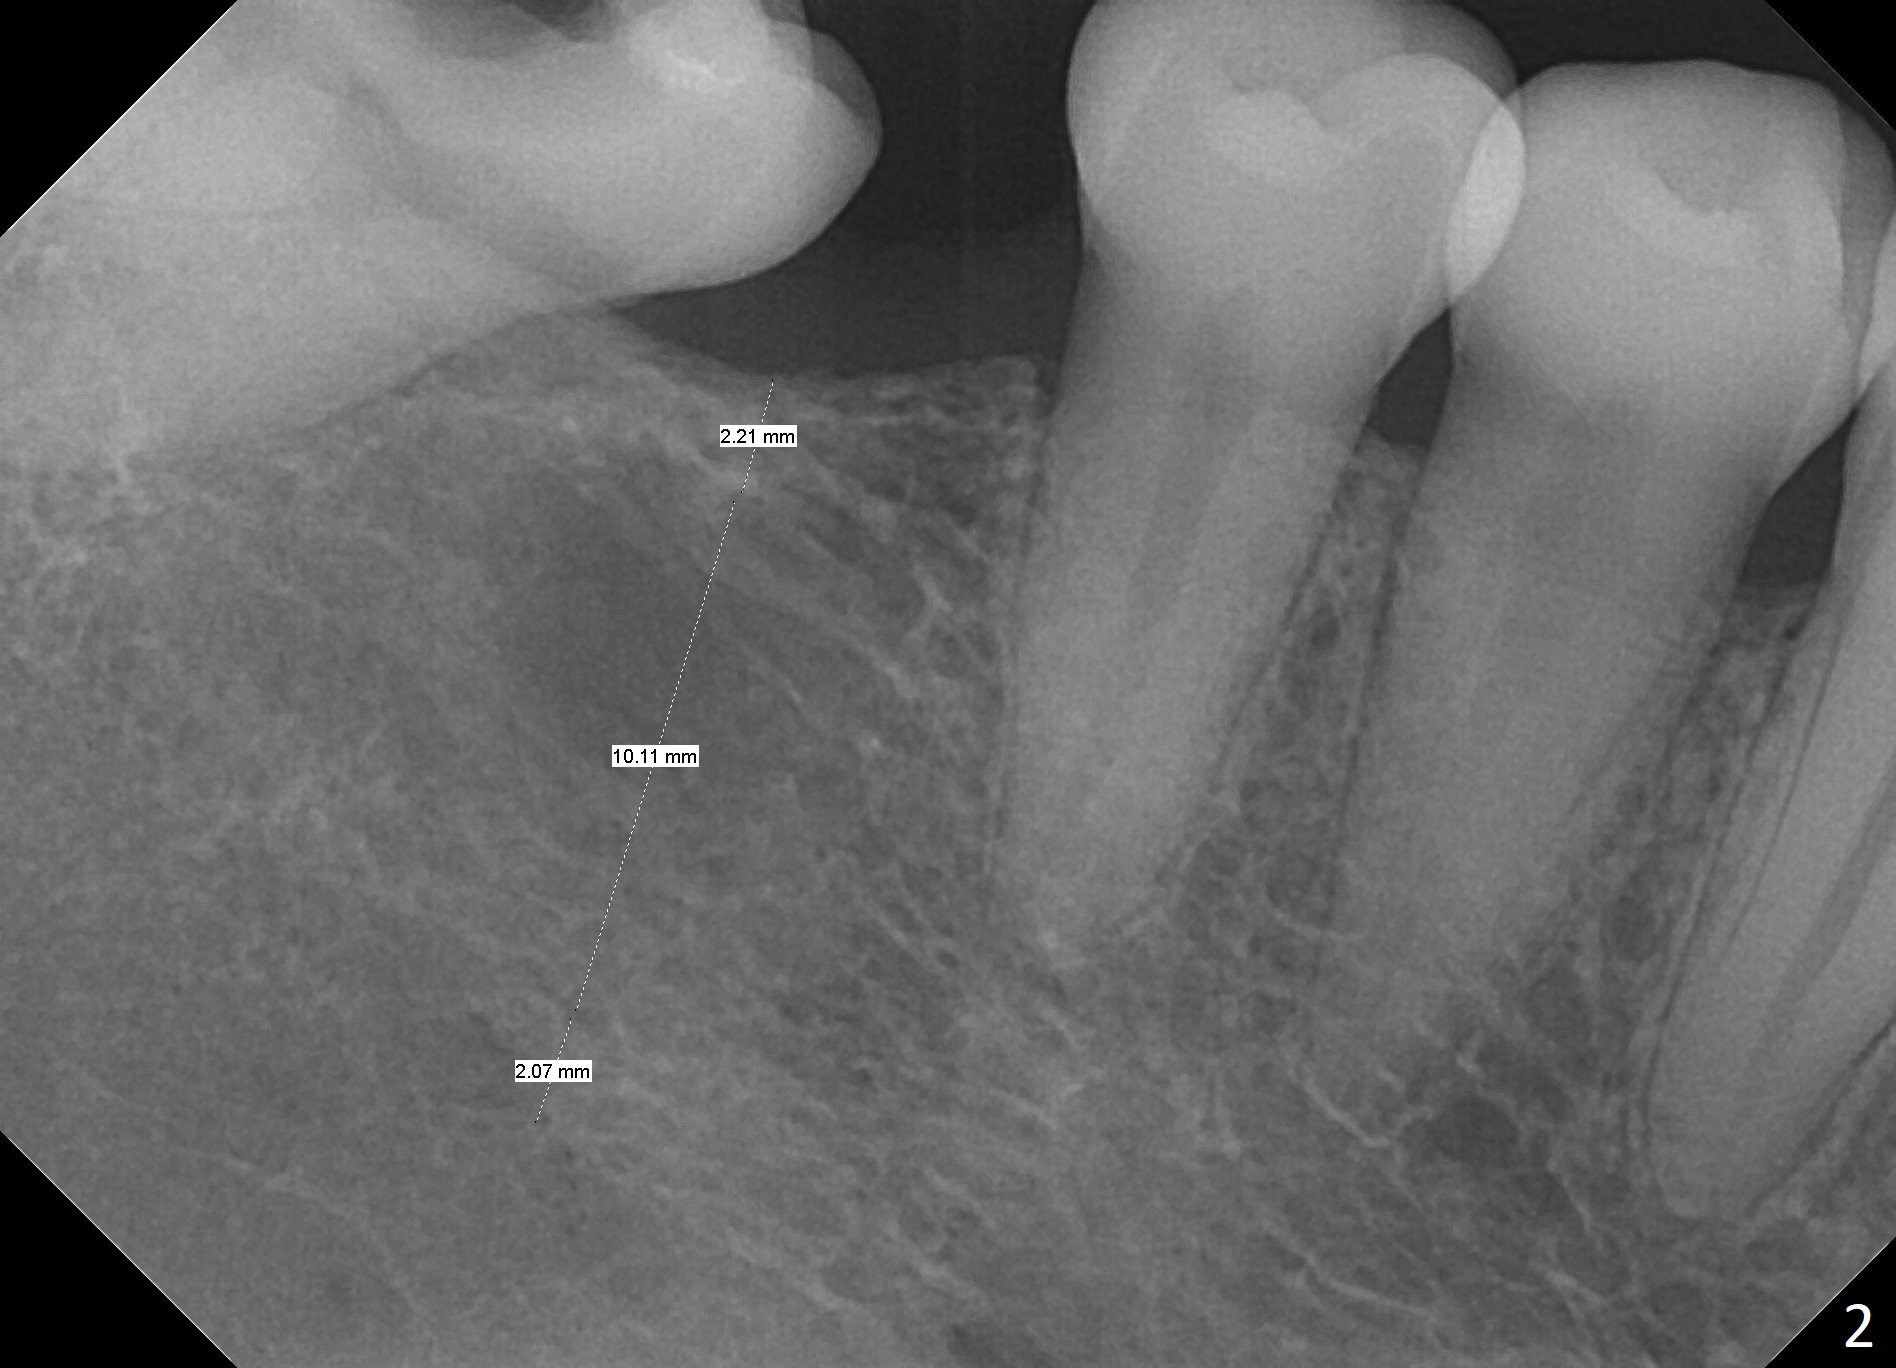

A 54-year-old woman has poor dentition (Fig.1). The teeth #3 and 4 have had composite with crowns and/or RCT pending, while IRM has been placed at #31. Since the temporary restoration is breaking down at #31, composite will be placed with Isolite. Crown prep will be also done at #31, especially mesially, and splinted provisional will be fabricated at #30 and 31 immediate following #30 implant placement. If the ridge at #30 is narrow, ridge reduction will be done with possible use of a 3.5x10 mm or 8.5 mm 1-piece implant (Tatum or IS, Fig.2). Prepare implant positioner. Under prepare the site because of low density bone.